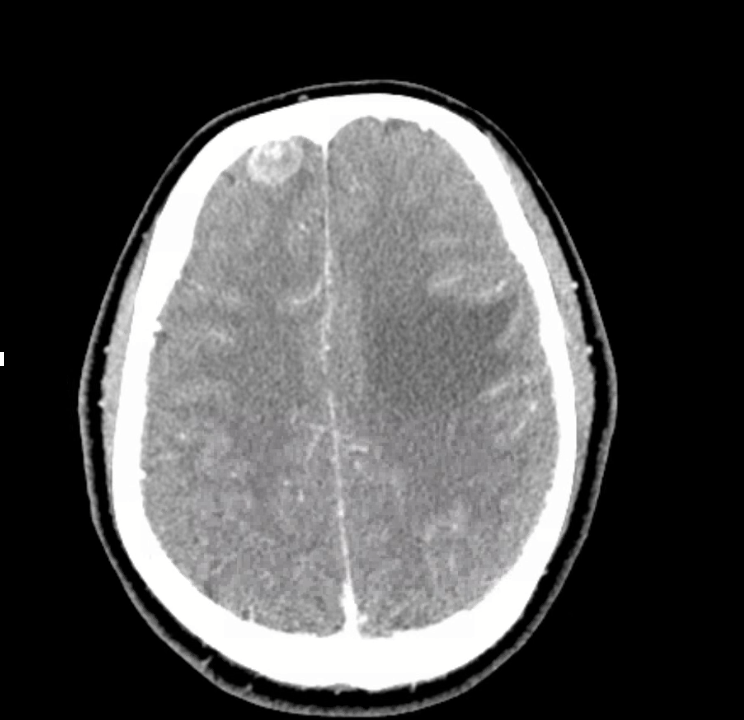

3) Neuro findings—ring-enhancing lesions

- Differential: septic emboli/abscess, nocardia, fungal, TB, parasites, metastases, vasculitis, sarcoid.

- Partner with neuroradiology for pattern nuances; treat seizures but keep searching for the unifying diagnosis.

- Therapy: Targeted TKI (crizotinib) → dramatic radiographic response of miliary lung disease and CNS lesions.

- Teaching point: even “miliary TB-like” lungs + CNS lesions in a 20-something can be driver-positive lung cancer—don’t let age or pattern blind you.